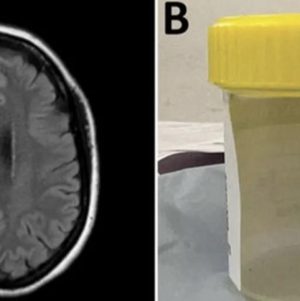

Haberde, Şalan’ın böbrek yetmezliği bulunan ve sepsis hastası kızı Meryem için de yiyecek ve ilaç aramak zorunda kaldığı, sık sık yardım çağrısında bulunduğu aktarıldı.